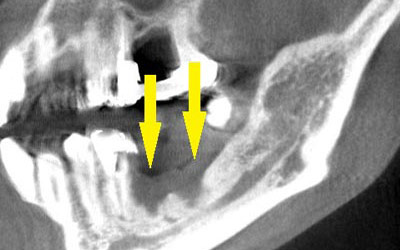

写真のように、CTで見ると、骨吸収の様子が良く分かり、下顎骨の中を通る神経近くまで骨がありませんでした。

さらに、CTで、別な方向から見ると、黄色矢印のように骨が吸収されていて、緑色矢印で示される神経の通る管に迫り、インプラントが埋入できるような骨量はありませんでした。

インプラントを埋入するために、骨を増やす方法はいくつかありましたが、この場合、患者様ご自身の骨をブロック状で移植するのが最も適していると判断し、自家骨移植術を行ないました。患者様ご自身の下顎前歯の下方から骨を採取して、骨がなかった部位に移植し、スクリューで固定したCT画像です。黄色矢印部分が、2つの骨片を移植して、固定したところです。

手術後の、別な方向からみたCT画像です。術前に大きく吸収されていた部分に、骨のブロックが移植され、骨が造成されています。真っ白にピンのように写るのは、骨を固定した小さなスクリューです。